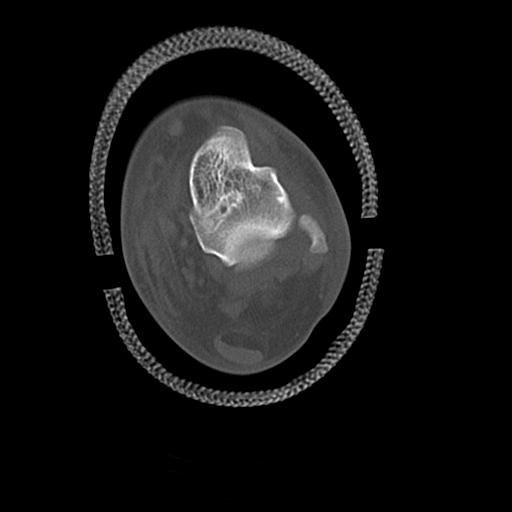

49554 3/13 膝 4R 3/16 4R 1/18 2R 78歳男性 膝蓋骨骨折